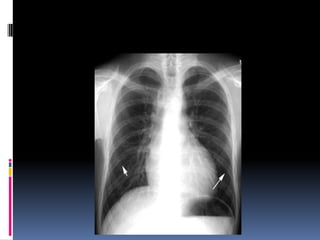

Positioning / Rotation

Does the thoracic spine align in the center of the

sternum and between the clavicles?

Clavicles – equidistant from spine

Determine side – ? L/R

 Gastric bubble should be on the left ( normally )